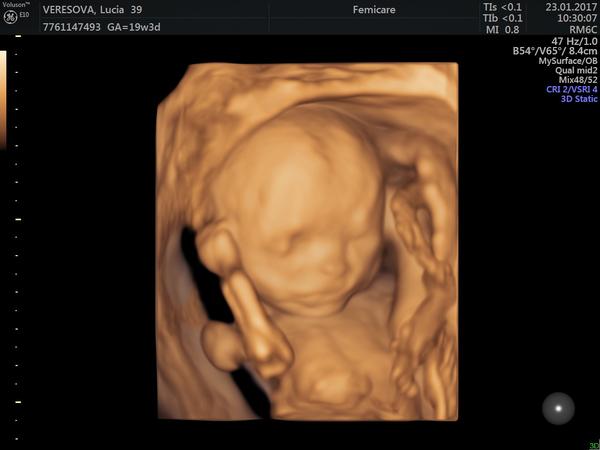

Môže takto vyzerať fotka z 3D/4D ultrazvuku?

ahojte, dnes som bola objednana na dlho ocakavaní 4D ultazvuk u pana Dandara(vo weberovom dome), bola som vsak sklamana ze na obrazovke vidim to iste co u svojej zenskej lekarky , ziadne detaily ako na obrazkach od inych tehuliek ci videach na intenete , fotku som dostala az po vyziadani pricom pri objednavani mi bolo povedane ze mam doniest usb ze je to v cene, fotku som dostala jednu na A4 a je to cista machula, moja lekarka mi robila krajsie zabery, za to vsetko pytali 42eur na blocku mam napisane Morfologia plus foto, a na peciatke v t.preukaze dokonca meno Poch co som ani netusila kedze ani pana Dandara som nikdy predtym nevidela takze som nevedela ako ma vizeret... bohuzial som to neriesila hned na mieste kedze mam povahu aku mam a trva mi kym sa zo soku spamatam, a teraz neviem ci to mam riesit alebo to fakt bolo ak nie 4D ako malo byt aspon 3D ako pisu na blocku.... ☹

4D znamena, ze vidis na UZV priamo pohyby babatka. kludne to mohlo byt 4D sono, ale fotku s pohybom ti nik nespravi, to by muselo byt video. cize fotka moze byt iba 3D alebo 2D. tvoja fotka vyzera ako 3D, pretoze je tam vidiet vypukliny do priestoru, takze sklamanie vyplyva iba z toho, ze si ocakavala kvalitnejsiu fotografiu... zrejme nemal lekar na to dostatocne dobry UZV, tieto pekne hnedo-ruzove fotky su este pocitacovo retusovane, aby vyzerali co najlepsie, na to treba fakt kvalitny pristroj... moj gynekolog v prvom tehotenstve mal tiez 4D sono a mam fotky porovnatelne s tvojou... pre mna vsak bolo skor dolezite vediet ze je maly v poriadku a fotim si ho teraz ked je medzi nami 🙂

To nie je 4D, je to klasicky ultrazvuk a ked tam je napísane morfológia, tak je to v poriadku. Ja som bola na morfológii v BA a fotka je presne takáto